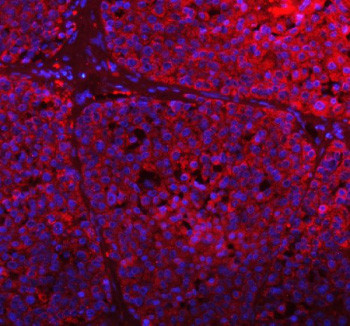

Adding 0.2 ml of distilled water will yield a concentration of 500 ug/ml. GCLC antibody detects Glutamate-cysteine ligase catalytic subunit, a key enzyme encoded by the GCLC gene located on chromosome 6p12.1. GCLC catalyzes the first and rate-limiting step in glutathione (GSH) biosynthesis, forming gamma-glutamylcysteine from glutamate and cysteine. This enzyme plays an essential role in maintaining redox homeostasis, detoxifying reactive oxygen species (ROS), and protecting cells from oxidative stress. GCLC is expressed ubiquitously, with highest levels in liver, kidney, and lung, where glutathione metabolism is most active.Structurally, GCLC is a 73 kDa cytosolic enzyme that functions as the catalytic component of the heterodimeric glutamate-cysteine ligase complex, together with the modifier subunit GCLM. It contains ATP-binding and substrate-recognition domains that mediate the ligation reaction. GCLC belongs to the ATP-dependent ligase family and serves as the principal control point in GSH biosynthesis. Co-localization studies show cytoplasmic distribution in metabolically active tissues, aligning with its antioxidant role.Functionally, GCLC maintains cellular antioxidant defenses by providing the precursor for glutathione synthesis. Glutathione serves as a cofactor for numerous detoxification enzymes, including glutathione peroxidases and glutathione S-transferases. Through GSH production, GCLC supports redox regulation, protein thiol homeostasis, and protection against electrophilic stress. In immune cells, GCLC-derived glutathione regulates T-cell activation and macrophage inflammatory responses. Known substrates include L-glutamate, L-cysteine, and ATP.Deficiency or dysregulation of GCLC results in decreased glutathione levels, leading to oxidative stress, hemolytic anemia, and liver dysfunction. Mutations in GCLC are associated with glutathione synthetase deficiency and neurological disorders linked to oxidative damage. Overexpression is observed in certain cancers, conferring chemoresistance through enhanced antioxidant capacity. Pathway associations include glutathione metabolism, oxidative stress response, and xenobiotic detoxification. During development, GCLC supports organogenesis by protecting proliferating cells from oxidative injury.The GCLC antibody from NSJ Bioreagents is an excellent reagent for studies involving redox biology, detoxification mechanisms, and glutathione metabolism.

| Application: | ELISA, FC, IF, IHC, WB |